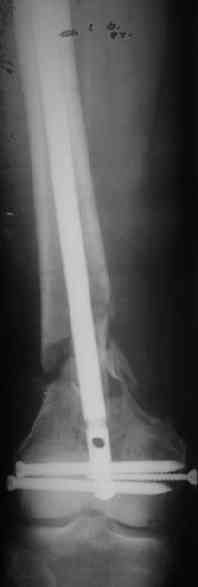

Looks like some callus response already seen suggesting that the healing

process is in progress though the X-ray alignment in AP view is not

appealing. Any open interference to improve the X-ray appearance could be a

bloody procedure and could lead to further de-vitalisation of bone. Also

shortening of 2cm in the lower limb is probably acceptable and can be easily

compensated by footwear adjustment.

It appears to me as if someone has already tried to "Mold" or contour this plate - there seems to be an extra angle in it. This plate should not be contoured, since the shape of it (the 95 degree angle) is what allows it to be used , when inserted correctly, to re-establish the relationship between the joint and shaft axes.

I think the primary problem is "simply" a translational one and not a major angular deformity. I wonder if the shortening is more related to contracture than loss of bone. I would obtain long alignment films (hip- knee-ankle), and perhaps a scanogram, or at least separate bilateral femur films, to try and sort these issues out.

I think I would favor treatment to healing in this position, with aggressive PT and then re-evaluate the extent of disability. Nutritional and medical optimization and a bone stimulator may be worth considering. The presence of a cerclage wire in an area of comminution is often forensic evidence of bone murder. I am not optimistic that a retrograde nail would lead to secure healing and would worry about taking it all apart at this stage.

Укорочение около 2 см. Движения в колене - 45

градусов.